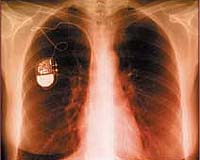

The tiny new batteries are indispensable in everything from pacemakers to the electronic stimulators that help restore function in the brains of Parkinson's patients.

Designed to be extraordinarily reliable and work continuously for years, the tiny batteries are indispensable in everything from pacemakers to the electronic stimulators that help restore function in the brains of Parkinson's patients.

However, lithium batteries don't last forever and new surgery to maintain many devices seeded into the body is required, as well as to replace batteries and devices at the end of their lives.

But Professor Emeritus of Chemistry Robert West and colleagues say the new lithium battery technology is capable of making batteries smaller, last longer and, soon, accept a charge from outside the body without the need for surgery.

Using organosilicon compounds, West's team has developed a generation of rechargeable lithium ion batteries with lifetimes more than twice as long as current medical device batteries.

A critical advantage of the new battery technology is lifespan: "If you're going to implant these things, you want a (battery) lifetime of at least 10 years," said West, whose organosilicon batteries are projected to power tiny implantable devices for more than 12 years.